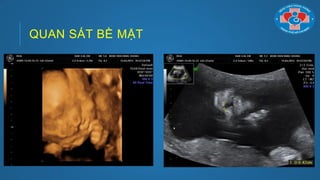

ỨNG DỤNG CỦA SIÊU ÂM 3D/4D

Quan sát bề mặt: (Sử dụng tốt nhất trên mặt, cột sống, tứ

chi)

QUAN SÁT BỀ MẶT